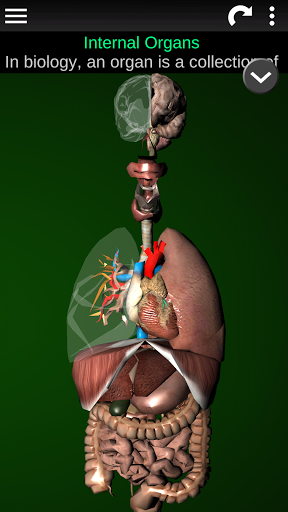

Toont een 3D-anatomisch model van de belangrijkste organen van het menselijk lichaam en een beschrijving van elk orgaan.

Wat zit er in de app?

* Spijsverteringsstelsel, inclusief de maag, dunne darm, dikke darm, en een animatie van dit systeem.

* Ademhalingssysteem, inclusief de luchtpijp, bronchiën, longen en een animatie van dit systeem.

* Voortplantingssysteem, dat de mannelijke en vrouwelijke voortplantingsorganen omvat.

* Hersenen, waaronder de hersenen, het cerebellum en de hersenstam vallen.

* Hart, dat de atria, ventrikels, aorta en een animatie van dit orgel omvat.

* Gemakkelijk te openen en te navigeren (zoom, 3D-rotatie).

* Beschrijvingen van elk orgel.

Deze app is ontworpen als aanvulling op de studie van anatomie in verschillende onderwijs-, gezondheidszorg- en culturele omgevingen.